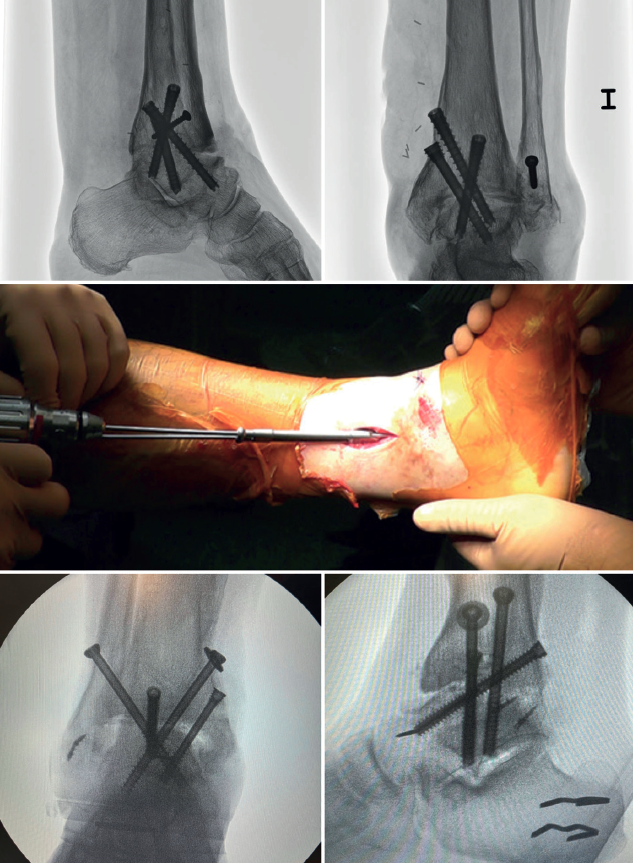

In arthroscopic ankle arthrodesis, the use of percutaneously placed compression screws is the technique of choice (Figure 5).

Most authors consider the use of cannulated screws (3 to 4) to be the ideal fixation method. The diameters of the chosen screws should be between 6 and 7 mm. This technique achieves 85-100% fusion and 84-95% patient satisfaction rates(19).

Van Dijk, Kerkhoffs et al.(20) reported excellent results with the use of three screws as the standardized method for ankle arthrodesis.

Screw configuration and placement

Depending on the deformity involved and according to preoperative planning, screw placement is carried out starting with the compression screw that counteracts the deformity.

In other words, in arthropathies with a varus component, we would start with a lateral screw, while in valgus misalignments the recommendation is to place the first screw from the medial side. The second screw should be on the side opposite to the first. Both should provide adequate compression between the joint surfaces(17).

In general, a minimum of three screws are used. The third screw is the so-called home run screw, the importance of which has been highlighted by Holt et al.(21). It is directed across the ankle from the posterior part of the tibia to the neck of the talus. A fourth screw may be used as an augmentation of the first, counteracting the main deformity.

Goetzmann et al.(22), in their review of 111 cases, supported the use of at least three screws for fixation of arthroscopic tibiotalar arthrodesis. The addition of a third screw appears to be associated with a lower risk of pseudarthrosis and shorter consolidation time. These effects can be attributed to an increased stability of the construct.

Glick, Myerson(23) et al. reported that the configuration conferring the greatest rigidity to the osteosynthesis comprises two screws from medial and one from the lateral side.

Figure 4. Preparation of the joint surfaces using different types of instruments: curettes, chisels or motorized drills. Final view after obtaining an optimal subchondral bed of the tibiotalar joint.